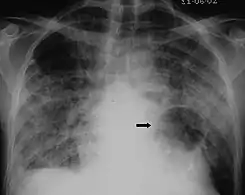

The diagnosis can be confirmed by the characteristic appearance of the chest X-ray and an arterial oxygen level (PaO2) that is strikingly lower than would be expected from symptoms. Gallium 67 scans are also useful in the diagnosis. They are abnormal in about 90% of cases and are often positive before the chest X-ray becomes abnormal. Chest X-ray typically shows widespread pulmonary infiltrates. CT scan may show pulmonary cysts (not to be confused with the cyst-forms of the pathogen).

Chest X-ray of increased opacification (whiteness) in the lower lungs.

X-ray of a cyst in pneumocystis pneumonia[7]